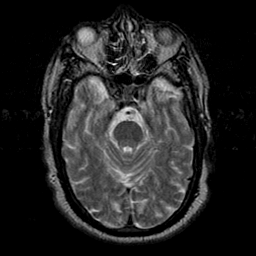

Subacute Stroke overlay -- Slice #7

[Home][Help][Clinical] Slice 7